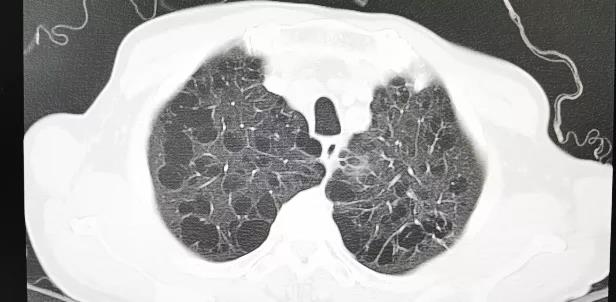

重度肺气肿、多发肺大泡 股动脉入路评估

患者男性,66岁,活动后胸闷气促3年,近1年内反复昏厥2次。术前心脏超声提示先天性二叶式主动脉瓣畸形伴重度狭窄、轻度反流,峰值流速4.4m/s,峰值压差89mmHg,平均跨瓣压差57mmHg,瓣口面积0.7cm2,同时心功能差,EF仅30%。CT评估显示主动脉瓣为Type I型二叶瓣,重度钙化,瓣环面积460.4mm2,测算直径24.2mm。左冠脉开口高度14.2mm,右冠脉开口高度13.7mm。患者合并重度肺气肿、多发性肺大泡,且心功能差,STS评分为3.2%,经多学科专家讨论,认为该患者不适合常规开胸外科手术,符合TAVI入组标准。